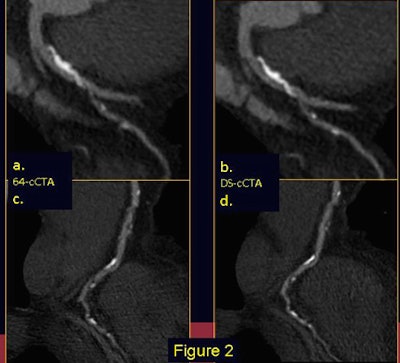

| Electrocardiogram-gated 64-slice CT (a-c) and dual-source CT (b-d) in a patient with an extensive calcified plaque of the anterior descending artery (a-b) and multiple atherosclerotic irregularities of the right coronary artery (c-d). DSCT, with its sharper delineation of heavily calcified plaque borders, allows a substantial reduction of blooming artifacts, thereby limiting overestimation of plaque burden. |